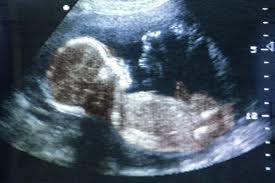

диагностировать беременность, в том числе внематочную и пр.

УЗИ во время беременности проводят:

- в первом триместре – в течение первых трех месяцев или до 12 недель – трансвагинальным методом с аналогичной подготовкой;

- во втором и третьем триместрах – проводят трансабдоминальным методом. Женщины, рожавшие с помощью операции кесарево сечение, исследование проходят с наполненным мочевым пузырем. Для женщин, рожавших самостоятельно и не рожавших – наполнение мочевого пузыря не является принципиальным.